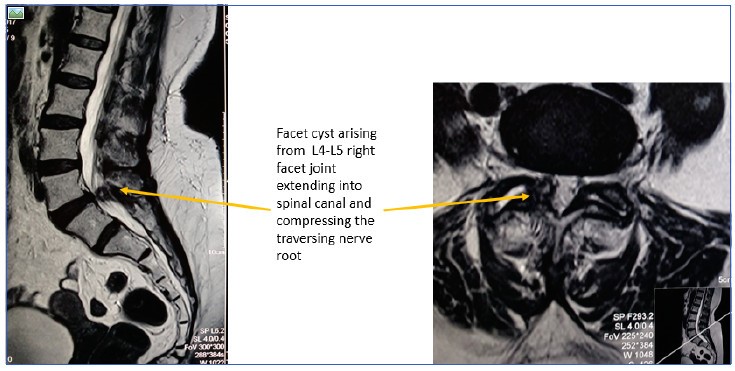

Trong tất cả các cuộc điều tra X quang, MRI đóng vai trò quan trọng nhất vì nó giúp phác họa các cấu trúc mô mềm một cách xuất sắc.

+ Khẳng định chẩn đoán thoát vị đĩa đệm và loại trừ các bệnh lý khác

+ Thể hiện kích thước đĩa đệm thoát vị

+ Thể hiện hình thái thoát vị: phồng đĩa đệm đối xứng, lồi đĩa đệm không đối xứng (không được coi là thoát vị đĩa đệm nhưng có thể gây ra các triệu chứng ở rễ), lồi đĩa đệm, lồi đĩa đệm rộng, lồi đĩa đệm và lồi đĩa đệm.11

+ Hiển thị vị trí thoát vị: trung tâm, cạnh trung tâm/dưới khớp, trong, ngoài lỗ

+ Cho biết có thoát vị đĩa đệm hay không

+ Thể hiện sự di chuyển của các mảnh: trên, dưới, nách, trong màng cứng12,13

+ Đánh giá mức độ tổn thương rễ thần kinh14

+ Đánh giá tình trạng sức khỏe của các đĩa đệm khác

+ Đánh giá kích thước lỗ thần kinh đĩa đệm

+ Quyết định xem bệnh nhân có thể được điều trị bảo tồn hay cần giải áp

+ Quyết định phương pháp phẫu thuật cho quy trình